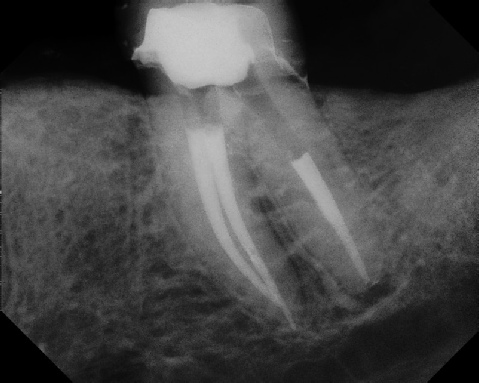

Pre-op Post-op 1 Post-op 2